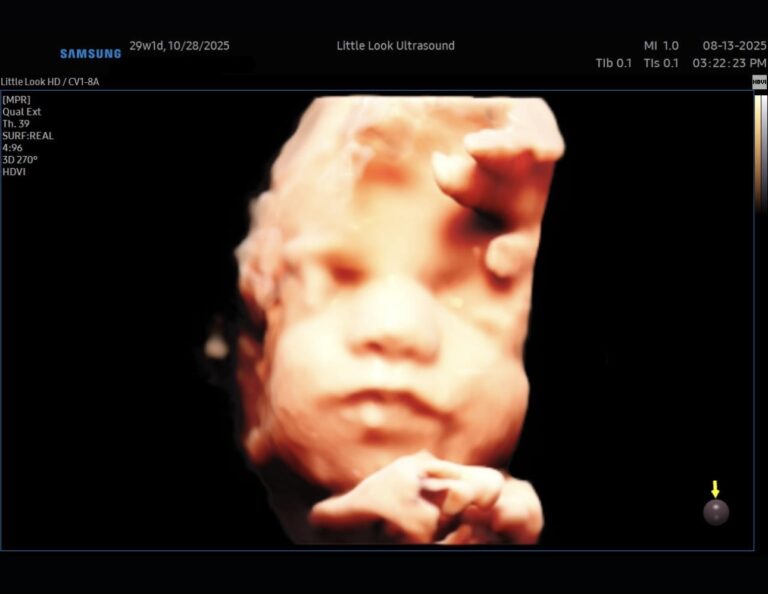

What Do Babies Look Like in the Womb? A Guide to Every Stage of Pregnancy NH MAExpectant parents in New Hampshire and Massachusetts often wonder what their little one looks like before birth. Thanks to the advancements in 3D ultrasounds, families can now see their baby’s development more clearly than ever. From those first tiny features to the moment they’re ready to enter the world, here’s a look at what your baby looks like…

Why 3D Elective Ultrasounds Make the Perfect Pregnancy Keepsake in Southern NH & Northern MAPregnancy is a once-in-a-lifetime experience, and every moment feels worth remembering. While traditional ultrasounds are special, 3D elective ultrasounds in southern NH offer a whole new way to bond with your baby — and create keepsakes you’ll cherish for years. A Window Into Your Baby’s WorldUnlike flat, black-and-white 2D scans, 3D ultrasounds provide lifelike images…

The Best Time for a 3D 4D UltrasoundIf you’re planning a 3D ultrasound in Londonderry, NH, timing is everything. Choosing the right stage of pregnancy can mean the difference between faint outlines and breathtaking images of your baby’s tiny face. When to BookThe ideal time for a 3D ultrasound is typically between 27 and 32 weeks. By this stage, your baby has…